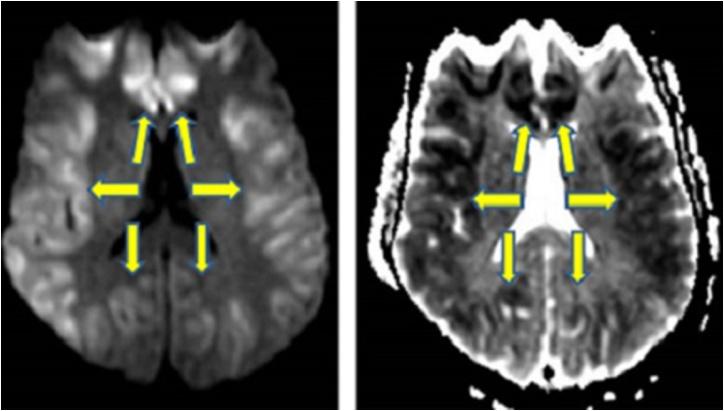

Acute encephalopathic syndromes can present a diagnostic challenge due to the wide range of possible etiologies, which also can have vastly different outcomes. The presence of diffuse cortical injury (DCI) on diffusion-weighted imaging (DWI) can help narrow the differential diagnosis. The aim of this review is to categorize the range of possible etiologies of DCI into a useful acronym, "CRUMPLED".

FINDINGS/DISCUSSION: The possible etiologies of DCI on DWI can be organized using the acronym "CRUMPLED": 'C' = Creutzfeldt-jakob disease, 'R' =  reversible cerebral vasoconstriction syndrome; 'U' = urea cycle disorders (hyperammonemia) and Uremia; 'M' = mitochondrial (cytopathy/encephalopathy); 'P' = prolonged seizure and posterior reversible encephalopathy (PRES); 'L' = laminar necrosis (hypoxic-ischemic encephalopathy) and liver disease (acute hepatic encephalopathy); 'E' = encephalitis (infectious meningoencephalitis); 'D' = diabetes mellitus (hypoglycemia). Other secondary imaging findings (outside of DWI) can be used to help differentiate between the aforementioned etiologies, such as the use of ADC maps, FLAIR imaging, intravenous contrast.

结果/讨论:DWI上DCI的可能病因可用首字母缩略词“CRUMPLED”来组织:“C”=克雅氏病;“R”=可逆性脑血管收缩综合征;“U”=尿素循环障碍(高氨血症)和尿毒症;“M”=线粒体(细胞病/脑病);“P”=癫痫持续状态和后部可逆性脑病(PRES);“L”=层状坏死(缺氧缺血性脑病)和肝病(急性肝性脑病);“E”=脑炎(感染性脑膜脑炎);“D”=糖尿病(低血糖)。其他次要影像学表现(DWI之外)可用于帮助区分上述病因,如使用表观扩散系数(ADC)图、液体衰减反转恢复(FLAIR)成像、静脉造影剂。